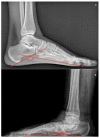

Adult acquired flatfoot deformity (AAFD) is a disorder caused by repetitive overloading, which leads to progressive posterior tibialis tendon (PTT) insufficiency. It mainly affects middle-aged women and occurs with foot pain, malalignment, and loss of function. After clinical examination, imaging plays a key role in the diagnosis and management of this pathology. Imaging allows confirmation of the diagnosis, monitoring of the disorder, outcome assessment and complication identification. Weight-bearing radiography of the foot and ankle are gold standard for the diagnosis of AAFD. Magnetic Resonance Imaging (MRI) is not routinely needed for the diagnosis; however, it can be used to evaluate the spring ligament and the degree of PTT damage which can help to guide surgical plans and management in patients with severe deformity. Ultrasonography (US) can be considered another helpful tool to evaluate the condition of the PTT and other soft-tissue structures. Computed Tomography (CT) provides enhanced, detailed visualization of the hindfoot, and it is useful both in the evaluation of bone abnormalities and in the accurate evaluation of measurements useful for diagnosis and post-surgical follow-up. Other state-of-the-art imaging examinations, like multiplanar weight-bearing imaging, are emerging as techniques for diagnosis and preoperative planning but are not yet standardized and their scope of application is not yet well defined. The aim of this review, performed through Pubmed and Web of Science databases, was to analyze the literature relating to the role of imaging in the diagnosis and treatment of AAFD.